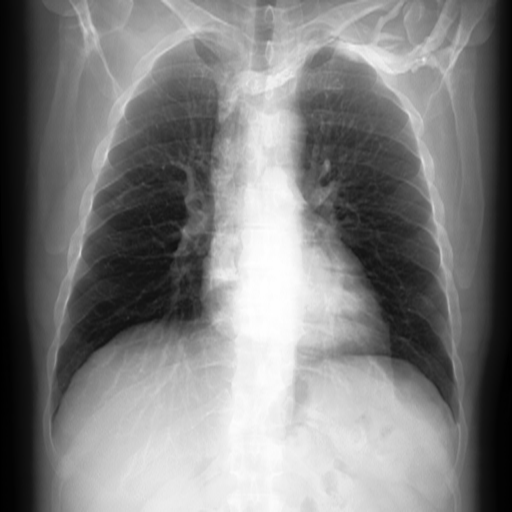

We compare our projected X-Rays with samples from the OpenI dataset for frontal and lateral views in Figure 5. The differences in the frontal view are due to the different positioning of the shoulder girdle. In the X-Rays, the arms are usually placed alongside the body, while in the projected images, the arms are raised due to the nature of the CT scan. In the lateral view, the X-Rays show a more comprehensive range of orientation and pose. However, the projected images, typically taken while the patient is lying down, result in similar poses between the different images. This leads to visual differences between images of female patients in both frontal and lateral views, such as the third column and second row of real X-Ray images and the first column and second row of projected images.